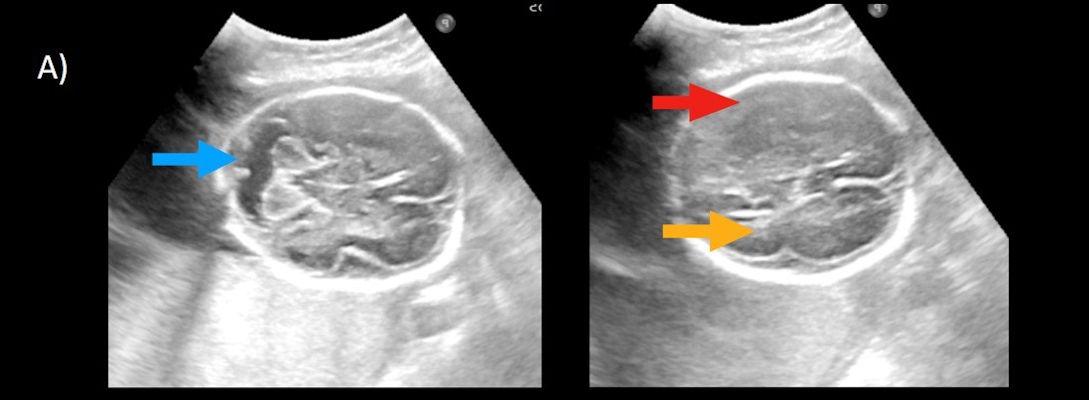

- A) USG incelemede serebral kortikal yapılar düzleşmiş (ok), gyrus sayısı azalmıştır (ok). Kalın ve ekojenik korteks mevcut olup korteks -beyaz cevher ayrımı silik görünümdedir. Posterior fossada ekstraaksiyel BOS mesafesi artmış görünümdedir (ok).

- B) Aksiyel ve sagittal T2A görüntülerde gyrus ve sulkuslarda azalma mevcut olup korteks kalınlaşmış görünümde ve operkulizasyon ayırt edilememiştir. Korteks beyaz cevher ayrımı zor seçilmektedir (ok) Ekstraaksiyel BOS mesafesi artmış görünümdedir (ok). Yapılan ölçümlerde; tegmentovermian açı :8 derece (ok) serebellar vermis boyutları kraniokaudal: 16 mm, aksiyel: 5,5×8,5 mm (ok) ölçülmüş olup BPD:27w ile uyumlu olan fetüste haftasıyla uygun olarak değerlendirilmiştir.